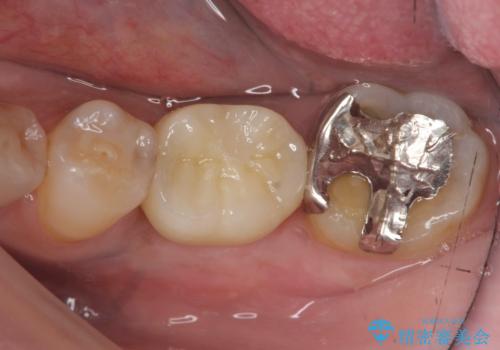

ブリッジや入れ歯といった周囲の歯の負担を増やす方法ではなく、より強大な咬合力にしっかりと耐え噛むことのできるインプラントを用いた機能回復を計画します。

- 34万円(税別)(ストローマンインプラント・アバットメント・仮歯・フルジルコニアクラウン)費用は治療当時の料金となります

今回の治療では、周囲の歯に負担を増やし破折リスクを高めるブリッジや入れ歯ではなくインプラント治療を選択しました。